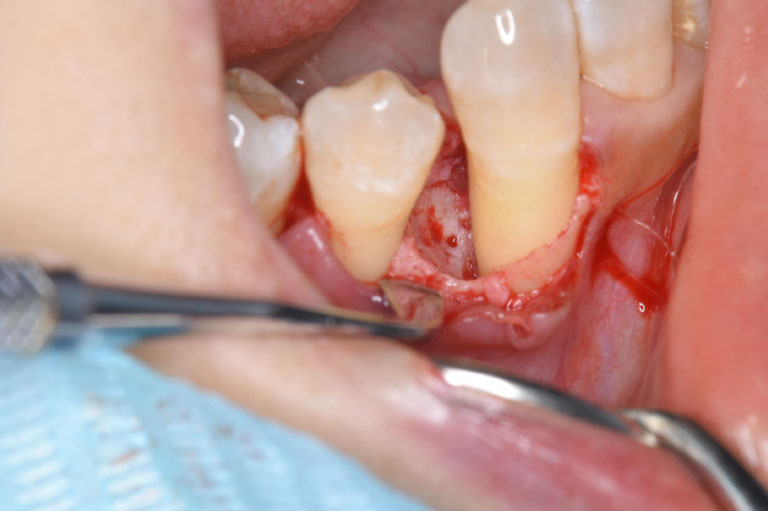

case.1

治療中

| 治療名 | 歯周組織再生療法 |

| 患者様情報 | 50代 女性 |

| 担当医 | 亀岡 聡貴 先生 |

| 費用 | 15.000円 (税込) 保険内 |

| 主訴 | 右下3番付近の歯茎が 1週間前から腫れている。 |

| 治療期間 | 1年 |

| 治療内容 | 歯周基本治療(SRP、TBI、咬合調整など)+歯周外科治療(再生療法)を行いました。全顎的に歯茎の炎症も落ち着き、レントゲン上でも骨の再生を認められました。 |

| 治療のリスク | 現在の状態の維持のため、継続的にメインテナンスを行う必要があります。 |